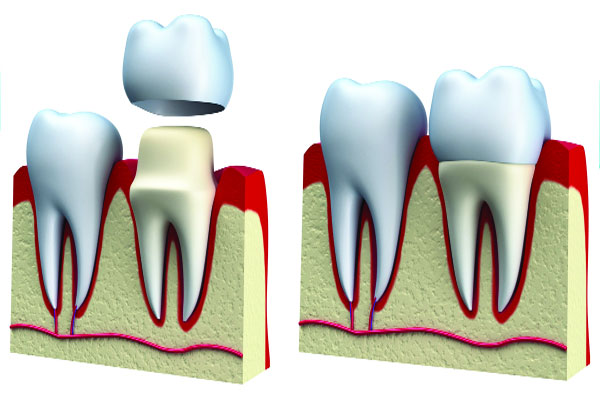

ডেন্টাল ক্রাউন বা ক্যাপ সম্পর্কে আমাদের কিছুটা ধারণা তো অবশ্যই আছে! ত্রুটিপূর্ণ দাঁতকে স্বাভাবিক রাখার জন্য চিকিৎসকরা ক্রাউন বা ক্যাপ ব্যবহারের পরামর্শ দিয়ে থাকেন। সাধারণত দাঁতে প্রদাহজনিত রোগ হলে সেই দাঁতে রুট ক্যানেল করার পর দাঁতটিকে স্বাভাবিক ও আবার যেন ভেঙে না যায় সে কারণে দাঁতে ক্যাপ পরানোর প্রয়োজন পরে। এ ছাড়া বিভিন্ন আঘাতে দাঁত ভেঙে যায় বা ফেটে যায় অথবা দাঁতের রং কালো হয়ে যায়। তখন দাঁতে ক্যাপ লাগানো জরুরি হয়ে পড়ে। দাঁতে শুধু ক্যাপ লাগালেই হবে না ক্যাপের সঙ্গে দাঁতের রঙের মিল থাকতে হবে। তা না হলে মুখের সৌন্দর্য নষ্ট হবে। তবে ক্যাপ লাগানো প্রক্রিয়া খুব সহজ কিছু নয়। অনেক সময় ক্যাপ লাগানোর পর নানা জটিলতা দেখা যায়। রুট ক্যানেল সঠিকভাবে সম্পন্ন না হওয়াকে এর অন্যতম কারণ বলে মনে করা হয়। অনেক সময় দাঁত সেপ অনুযায়ী কাটার সময় অসচেতন থাকলে মাড়িতে আঘাত লাগে। এ জন্য দাঁতে শিরশির অনুভূত হতে পারে। অনেক সময় এখান থেকে ডেন্টাল ক্যারিজ বা প্রদাহজনিত রোগ দেখা দিতে পারে। অনেক সময় অসতর্কতায় ক্যাপের মেকানিক্যাল লক নষ্ট হয়ে যায়। এতে ক্যাপ লাগানোর ব্যবহৃত উপাদানের মৌলিক গুণাগুণ নষ্ট হয়ে অনেক সময় ক্যাপটি দাঁত থেকে খুলে যায়। ডেন্টাল ক্রাউন বা ক্যাপ ধাতব পদার্থ দিয়ে তৈরি। ফলে পাশের দাঁতে খাবার জমে থাকার সম্ভাবনা বেশি থাকে। পরবর্তীতে দাঁত ও মাড়িতে রোগ হওয়ার সম্ভাবনা থাকে। অনেক ক্ষেত্রে ক্যাপ পরানো দাঁতের পাশের মাড়ি ধীরে ধীরে সরে যায়। এতে দাঁতের গোড়ার শক্তি কমে যায়। এক সময় দাঁত পড়ে যাওয়ার সম্ভাবনাও থাকে। আধুনিক ক্যাপের উপরিভাগ পরচিলিন দিয়ে তৈরি করা হয়। ফলে তা দাঁতের রঙের সঙ্গে মিলিয়ে করা হয়। যদি কোনো কারণে তা ত্রুটিপূর্ণ হয়ে থাকে সেক্ষেত্রে ক্যাপের উপরিভাগে ফাটল ধরে। এক সময় ফাটা অংশটি ধারালো হওয়ার কারণে জিহ্বা বা মুখের ভিতরের অংশ আঘাতপ্রাপ্ত হয়ে নানা প্রদাহ রোগ দেখা দিতে পারে।

ডেন্টাল ক্রাউন বা ক্যাপ সম্পর্কে আমাদের কিছুটা ধারণা তো অবশ্যই আছে! ত্রুটিপূর্ণ দাঁতকে স্বাভাবিক রাখার জন্য চিকিৎসকরা ক্রাউন বা ক্যাপ ব্যবহারের পরামর্শ দিয়ে থাকেন। সাধারণত দাঁতে প্রদাহজনিত রোগ হলে সেই দাঁতে রুট ক্যানেল করার পর দাঁতটিকে স্বাভাবিক ও আবার যেন ভেঙে না যায় সে কারণে দাঁতে ক্যাপ পরানোর প্রয়োজন পরে। এ ছাড়া বিভিন্ন আঘাতে দাঁত ভেঙে যায় বা ফেটে যায় অথবা দাঁতের রং কালো হয়ে যায়। তখন দাঁতে ক্যাপ লাগানো জরুরি হয়ে পড়ে। দাঁতে শুধু ক্যাপ লাগালেই হবে না ক্যাপের সঙ্গে দাঁতের রঙের মিল থাকতে হবে। তা না হলে মুখের সৌন্দর্য নষ্ট হবে। তবে ক্যাপ লাগানো প্রক্রিয়া খুব সহজ কিছু নয়। অনেক সময় ক্যাপ লাগানোর পর নানা জটিলতা দেখা যায়। রুট ক্যানেল সঠিকভাবে সম্পন্ন না হওয়াকে এর অন্যতম কারণ বলে মনে করা হয়। অনেক সময় দাঁত সেপ অনুযায়ী কাটার সময় অসচেতন থাকলে মাড়িতে আঘাত লাগে। এ জন্য দাঁতে শিরশির অনুভূত হতে পারে। অনেক সময় এখান থেকে ডেন্টাল ক্যারিজ বা প্রদাহজনিত রোগ দেখা দিতে পারে। অনেক সময় অসতর্কতায় ক্যাপের মেকানিক্যাল লক নষ্ট হয়ে যায়। এতে ক্যাপ লাগানোর ব্যবহৃত উপাদানের মৌলিক গুণাগুণ নষ্ট হয়ে অনেক সময় ক্যাপটি দাঁত থেকে খুলে যায়। ডেন্টাল ক্রাউন বা ক্যাপ ধাতব পদার্থ দিয়ে তৈরি। ফলে পাশের দাঁতে খাবার জমে থাকার সম্ভাবনা বেশি থাকে। পরবর্তীতে দাঁত ও মাড়িতে রোগ হওয়ার সম্ভাবনা থাকে। অনেক ক্ষেত্রে ক্যাপ পরানো দাঁতের পাশের মাড়ি ধীরে ধীরে সরে যায়। এতে দাঁতের গোড়ার শক্তি কমে যায়। এক সময় দাঁত পড়ে যাওয়ার সম্ভাবনাও থাকে। আধুনিক ক্যাপের উপরিভাগ পরচিলিন দিয়ে তৈরি করা হয়। ফলে তা দাঁতের রঙের সঙ্গে মিলিয়ে করা হয়। যদি কোনো কারণে তা ত্রুটিপূর্ণ হয়ে থাকে সেক্ষেত্রে ক্যাপের উপরিভাগে ফাটল ধরে। এক সময় ফাটা অংশটি ধারালো হওয়ার কারণে জিহ্বা বা মুখের ভিতরের অংশ আঘাতপ্রাপ্ত হয়ে নানা প্রদাহ রোগ দেখা দিতে পারে।